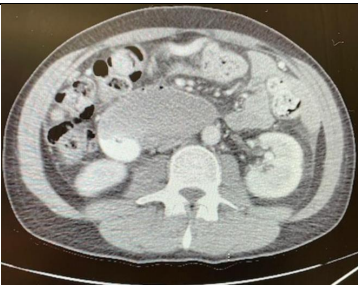

The patient is a 48-year-old male who was diagnosed with metastatic pancreatic cancer in November 2023. The primary cancer was from the body of the pancreas with metastatic disease to the liver and lymph nodes. He developed severe duodenal obstruction and was unable to eat or drink. The CT scan showed obstruction at the duodenojejunal junction. The computed tomography showed upstream dilation of the stomach and duodenum (Figures 1 and 2). He was evaluated for EUS-GE.

Figure 1. Showing duodenal obstruction from pancreatic body cancer